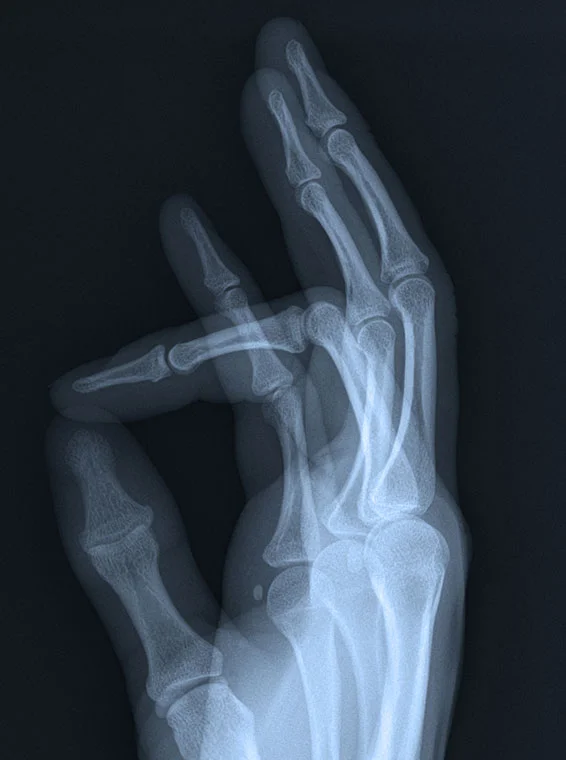

SURGICAL PROCEDURES & CONDITIONS OF THE HAND & WRIST

Surgery for Finger Joint Arthritis